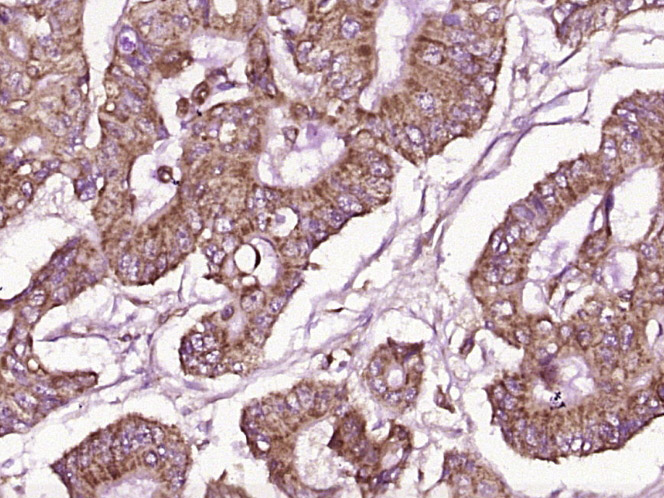

Tissue/cell: human gastric carcinoma; 4% Paraformaldehyde-fixed and paraffin-embedded; Antigen retrieval: citrate buffer ( 0.01M, pH 6.0 ), Boiling bathing for 15min; Block endogenous peroxidase by 3% Hydrogen peroxide for 30min; Blocking buffer (normal goat serum,C-0005) at 37℃ for 20 min; Incubation: Anti-GPA33 Polyclonal Antibody, Unconjugated(bs-1226R) 1:200, overnight at 4°C, followed by conjugation to the secondary antibody(SP-0023) and DAB(C-0010) staining